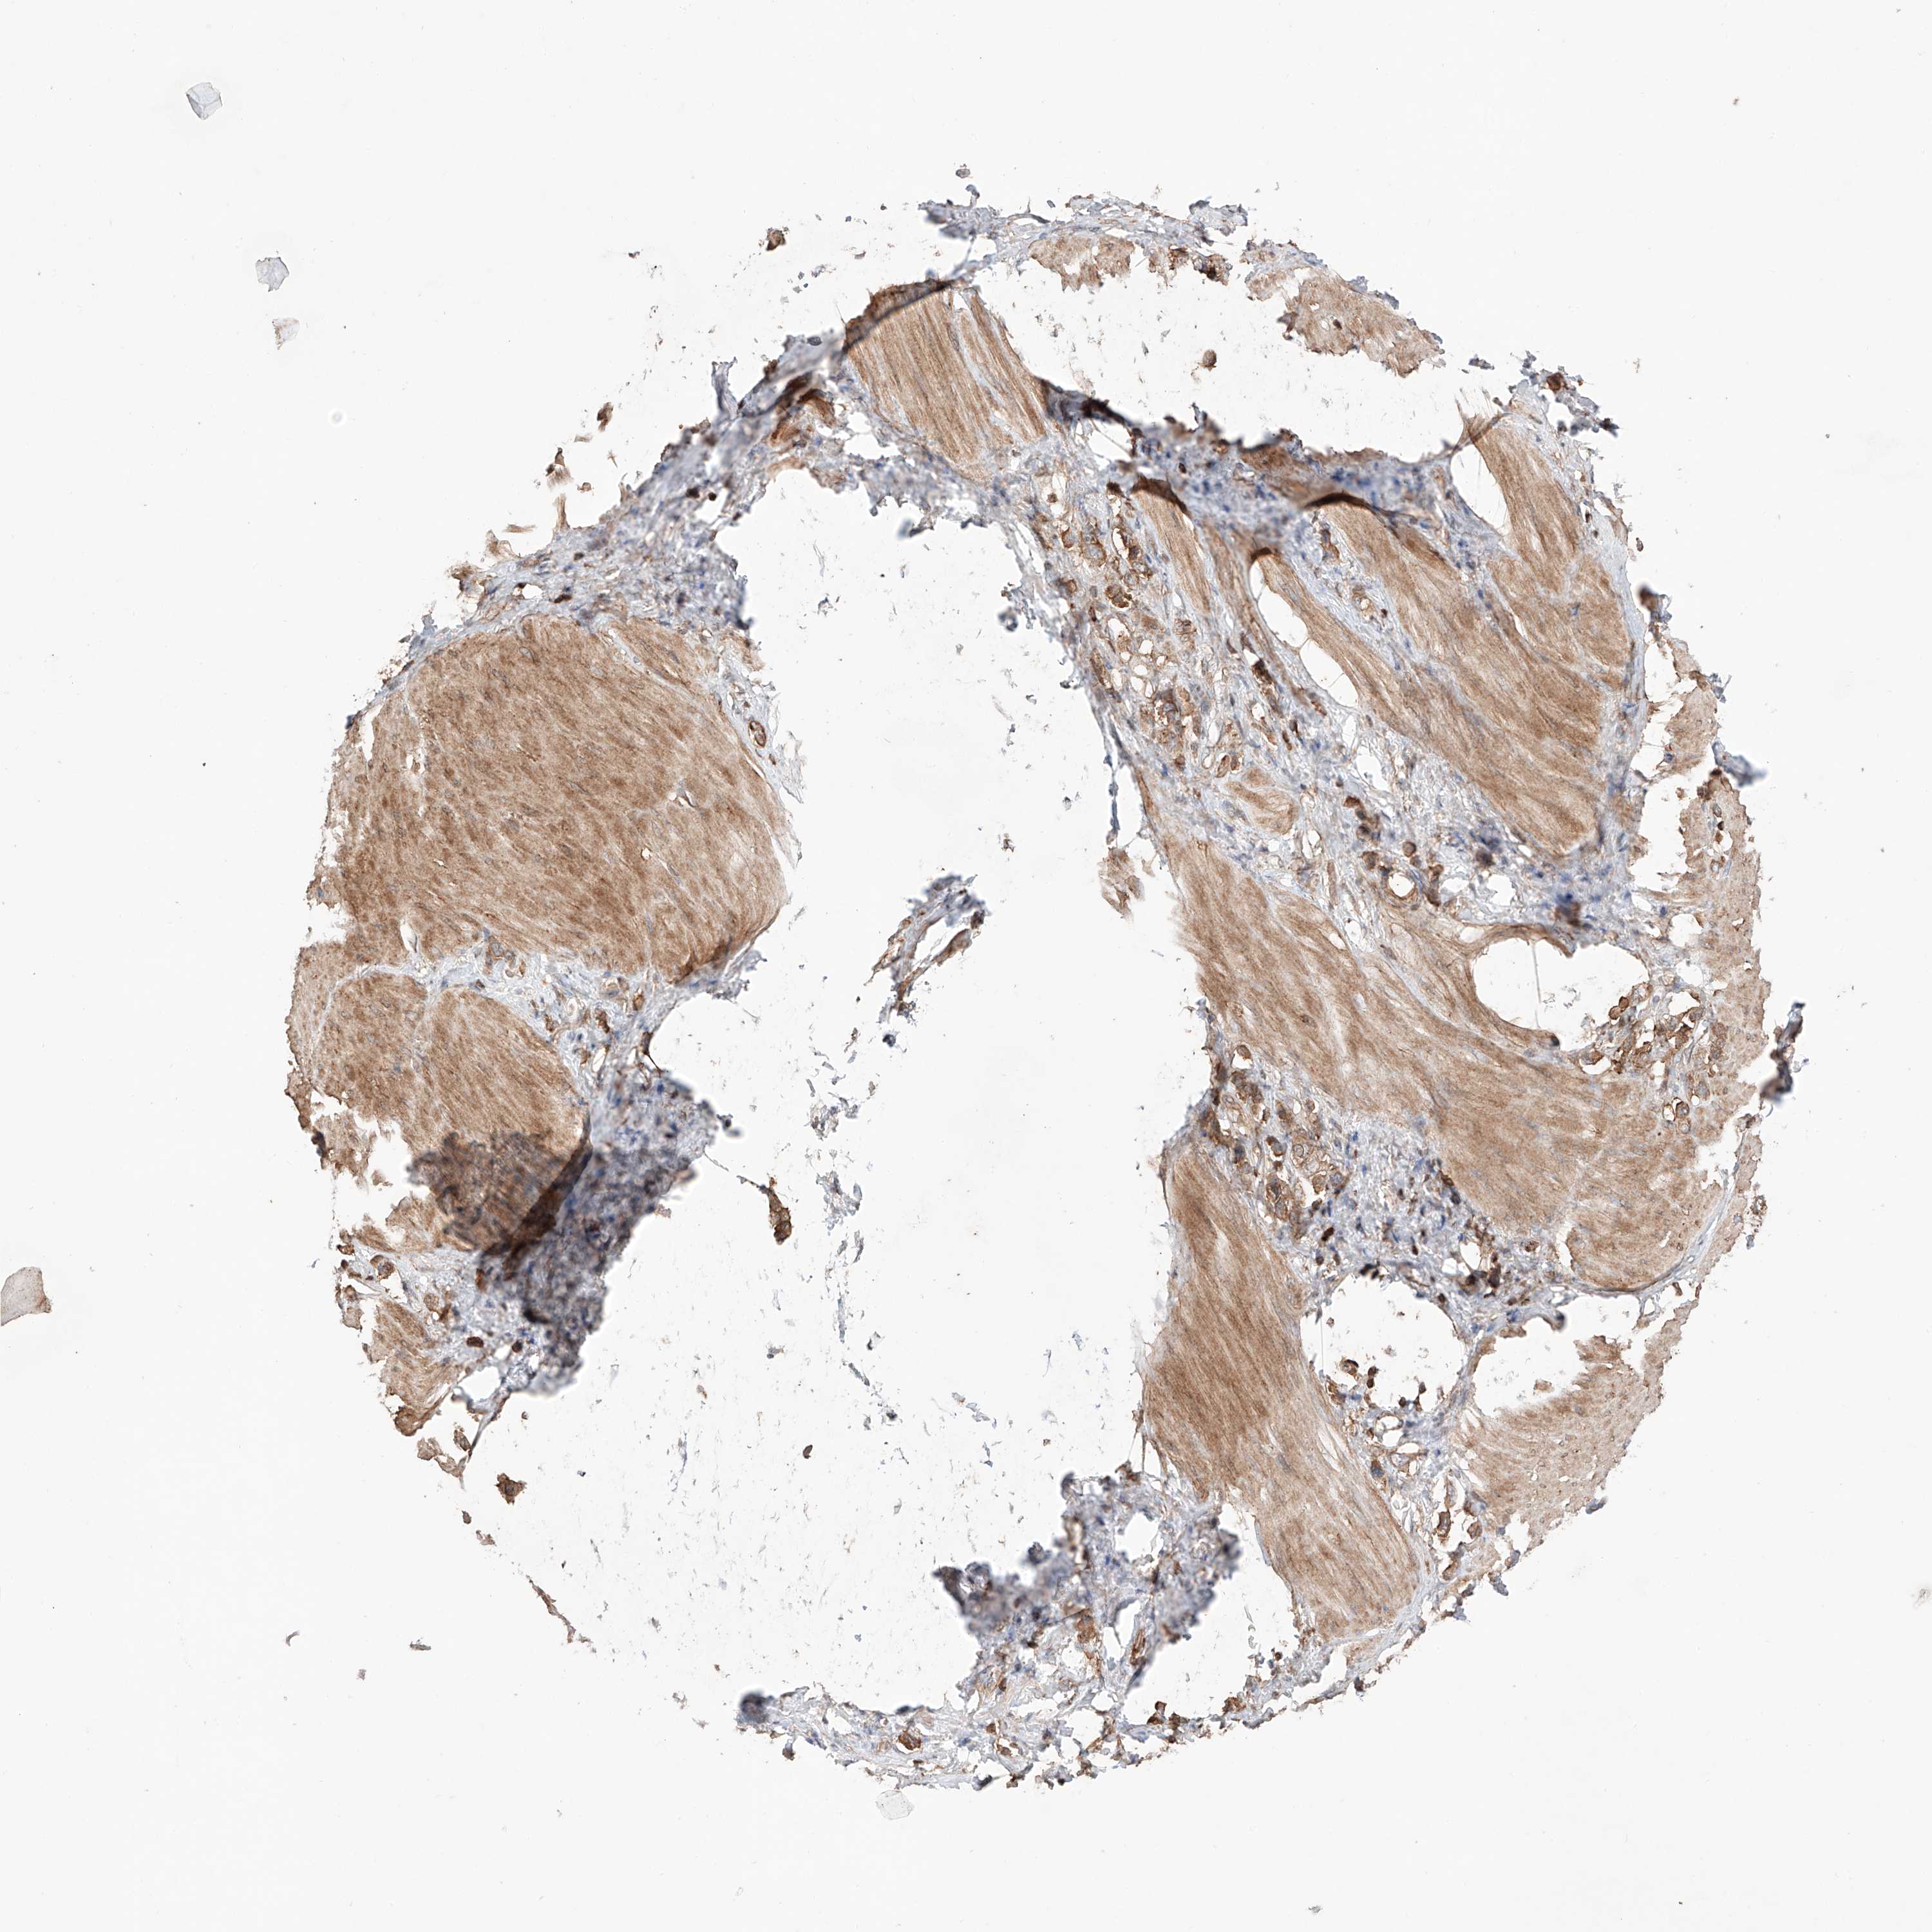

STOMACH CANCER - Protein expressioni

A mouse-over function shows sample information and annotation data. Click on an image to view it in a full screen mode. Samples can be filtered based on level of antibody staining by selecting one or several of the following categories: high, medium, low and not detected. The assay and annotation is described here.

Note that samples used for immunohistochemistry by the Human Protein Atlas do not correspond to samples in the TCGA dataset.

Antibody stainingi

Antibody staining in the annotated cell types in the current human tissue is reported as not detected, low, medium, or high, based on conventional immunohistochemistry profiling in selected tissues. This score is based on the combination of the staining intensity and fraction of stained cells.

Each image is clickable and will lead to virtual microscopy that enables deeper exploration of all samples and also displays staining intensity scores, fraction scores and subcellular localization as well as patient and tissue information for each sample.

Antibody CAB026459

Staining

High

Medium

Low

Not detected

Intensity

Strong

Moderate

Weak

Negative

Quantity

>75%

75%-25%

<25%

None

Location

Nuclear

Cytoplasmic/membranous

Cytoplasmic/membranous,nuclear

Adenocarcinoma, NOS